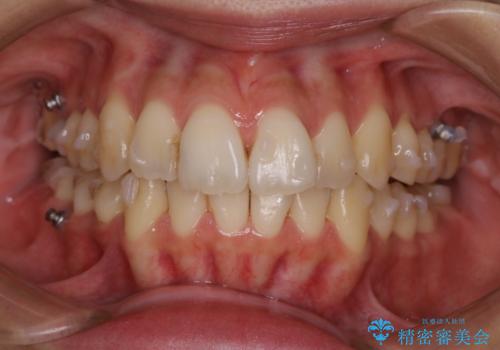

PMTC60分コースを行いました。

ステインとプラークが内側外側にとても多く付いていました。

タバコも吸うそうで、ステインが多かったです。60分コースでもギリギリ終わるくらいの汚れの量だったため、定期的にクリーニングやメンテナンスを行うようにおすすめしました。